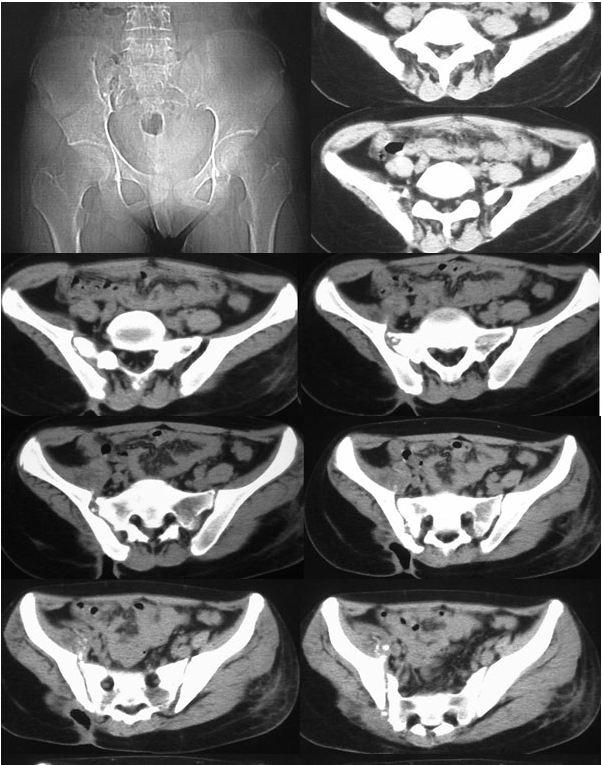

我的好友丹丹,老家有一个表妹,今年16岁,1年前无明显诱因出现右臀部酸痛,伴畏寒、发热、午后低热、盗汗,无双下肢放射痛,并出现左臀部皮肤红肿、破溃、流脓,曾在当地卫生院间断诊治,予以口服药物治疗,效果差,后逐渐出现右臀部外侧皮肤破溃、流脓,经自行口服药物后窦道自行愈合后,周围再次出现流脓,经久不愈,时有脓液流出。丹丹前两天回到老家,把表妹接到我院住院治疗。骨科专科检查发现右臀部一个约0.5x0 5 cm大小窦道口,按压周围可见黄色干酪样分泌物流出,局部可见肉芽组织,无红肿,周围可见多个窦道口疤痕。胸部X线检查:右上.中肺野及左中肺野可见片状.斑片(点)状.条索状阴影,边缘清晰,密度均匀。骨盆CT检查:右侧骶髂关节面骨质破坏、硬化,正常关节结构破坏,臀部软组织内可见囊性密度不均之肿块,影像诊断:右上.中肺.左中肺结核,右侧骶髂关节结核伴髂内肌冷脓肿形成、关节半脱位。

骶髂关节结核常见影像学表现为骨质破坏,死骨形成,关节间隙增宽或变窄,周围脓肿形成,部分伴有窦道。骨盆的X线平片检查可明显的看出骨质的改变,部分脓肿,但由于解剖结构的特殊性,无法显示全部的关节间隙。CT的密度分辨率较高,能够清晰的显示骨破坏程度、部位以及范围,对死骨、脓肿的形成及部位、窦道、囊肿等能够直观的检查,可以发现到X线检查难以观测的生理性骨化和病理性改变。

骶髂关节结核影像学表现:滑膜型结核早期关节囊肿胀,关节间隙增宽,继而侵及关节软骨和关节面;骨型结核早期在骶髂关节的骶骨或髂骨端见到孤立的圆形或椭圆形破坏区,边缘清楚,继而病变累及关节软骨和滑膜,导致关节边缘模糊、毛糙,骶髂关节前下部受累最早,且以髂骨侧破坏最严重。随着病变的进展,滑膜被增生的肉芽组织替代,干酪样坏死物聚集、侵蚀,死骨形成,最终使全关节受累,韧带软化、松弛,关节间隙增宽,这有别于其他大关节。由于骶髂关节结核的骨质疏松常不如其他关节明显,而往往显示有骨质增生硬化征象。关节破坏严重者,可造成病理性半脱位。大多有冷脓肿形成,多发生在臀部,有时在腹股沟、髂窝区,当脓肿增大,张力增高时,常自行破溃并沿着薄弱的组织间隙蔓延形成窦道。

骶髂关节结核典型CT表现:

(1)骨型骶髂关节结核呈圆形或椭圆形破坏区,并累及髂骨侧关节面。

(2)滑膜型骶髂关节结核呈:①关节面模糊、破坏,骨质破坏,关节间隙狭窄或不规则增宽;②大块死骨或散在颗粒状高密度影;③骨质增生硬化。